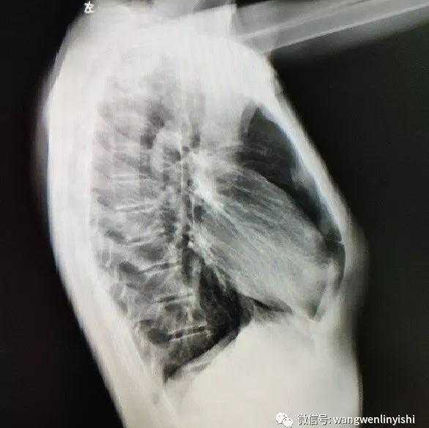

The patient is a 15-year-old teenage boy who has had severe pectus carinatum since childhood. Despite trying various methods to correct the deformity, such as taking calcium and cod liver oil supplements, and actively participating in sports, none of these have worked.

The anterior chest wall was significantly protruded, with a slight depression on the lower half of the chest wall.

First, a 2 cm incision was made on each side of the chest wall, and three support bars were inserted. Two of the bars were placed on the protruding bone structures to correct the pectus carinatum with the Wenlin procedure, while the third bar was positioned inside the chest cavity to address the depression using the Wung procedure. After the surgery, the patient’s chest deformity was corrected, and the chest wall’s appearance returned to normal.